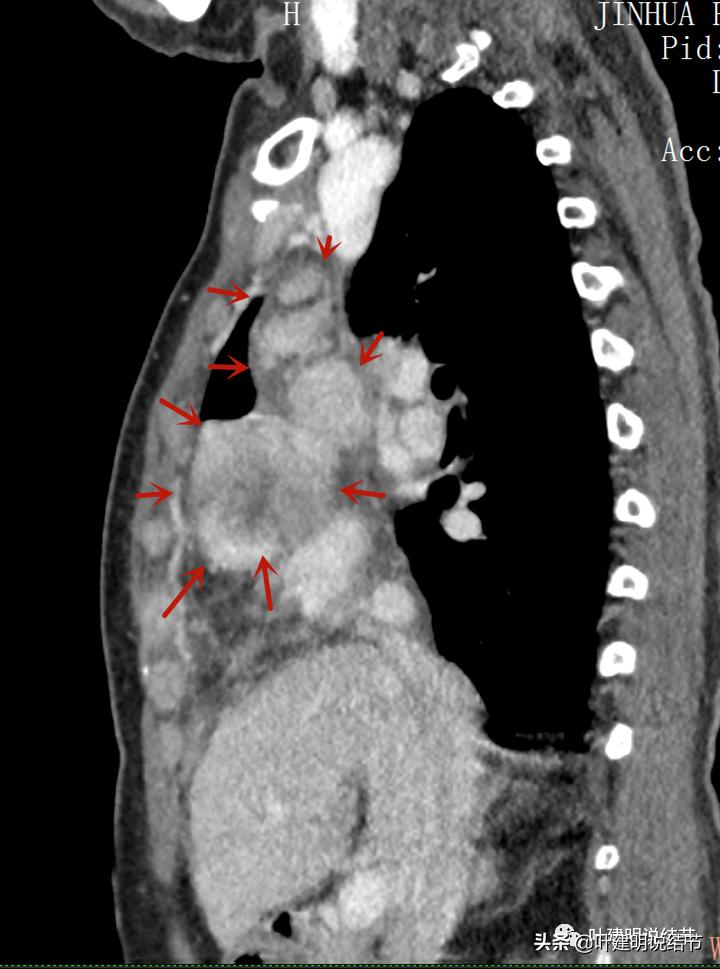

再来看看她的CT增强图像:

以下图片左侧是肺窗,右侧是纵隔窗。红色箭头示病灶,桔色箭头示无名静脉,黄色箭头示支气管,砖色箭头示上腔静脉,蓝色箭头示主动脉,紫色箭头示肺动脉。

病灶之间似不相连的,矢状位上见从上到下延续的

病灶占据前纵隔从上到下全程,多中心,密度不均,对心脏与大血管有压迫,没有明显侵犯

病灶表面不平,中间有坏死

特别显示与无名静脉的关系